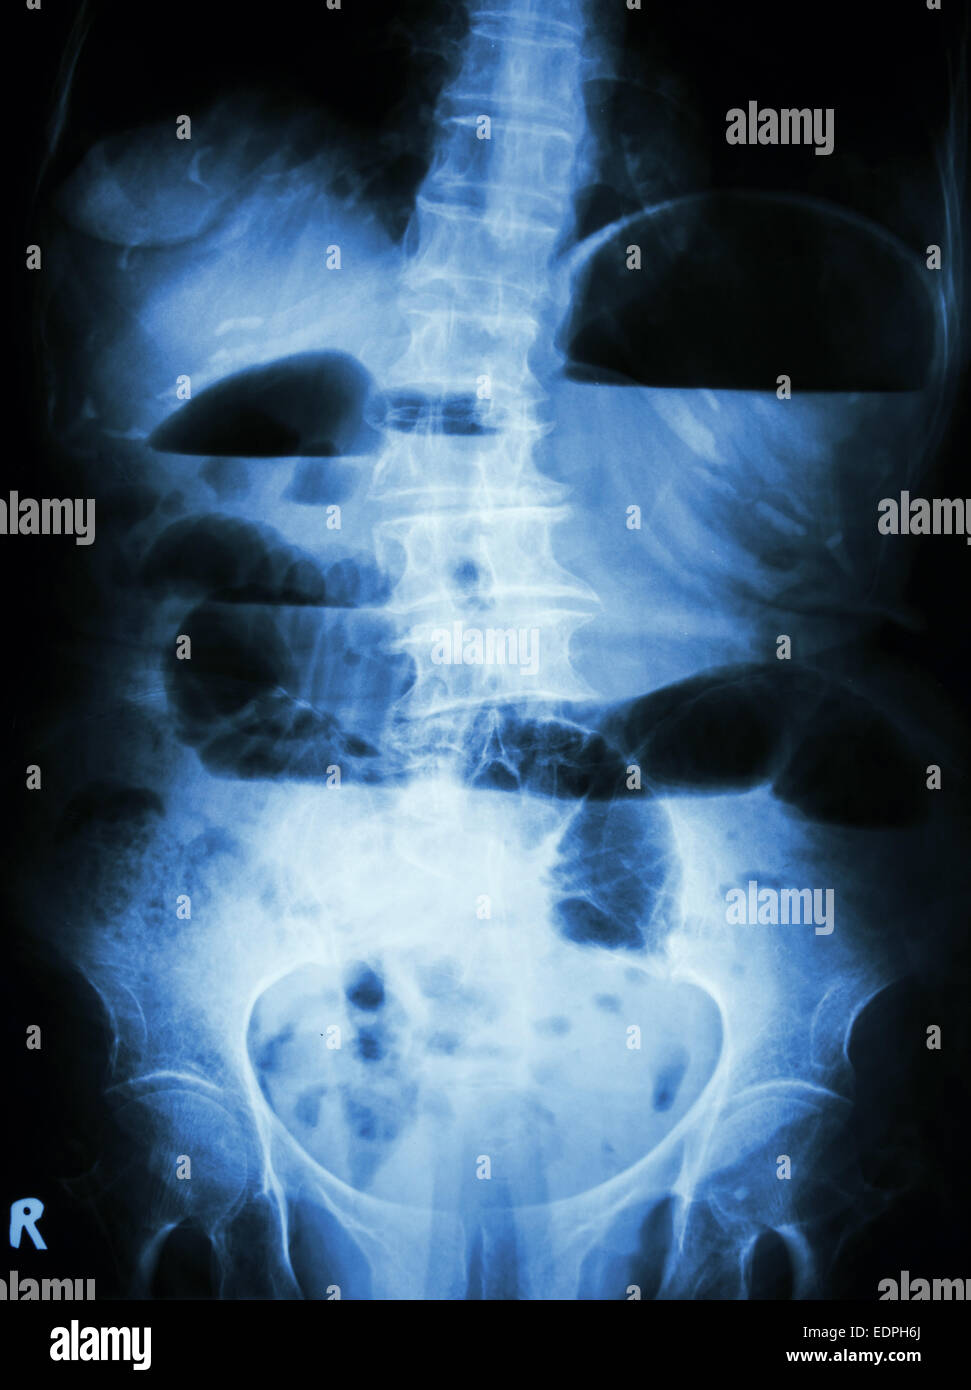

From www.alamy.com

Film Xray abdomen supine show small bowel dilated and air in small Do X Rays Show Intestinal Blockage Differentiate true mechanical obstruction from ileus or. Surgery to remove the obstruction is often needed. The main aims of imaging in cases of suspected bowel obstruction are: In this guide we use the bbc approach: Ct abdomen & pelvis with iv contrast: It can also be done to find an object that has been swallowed or to look for a. Do X Rays Show Intestinal Blockage.